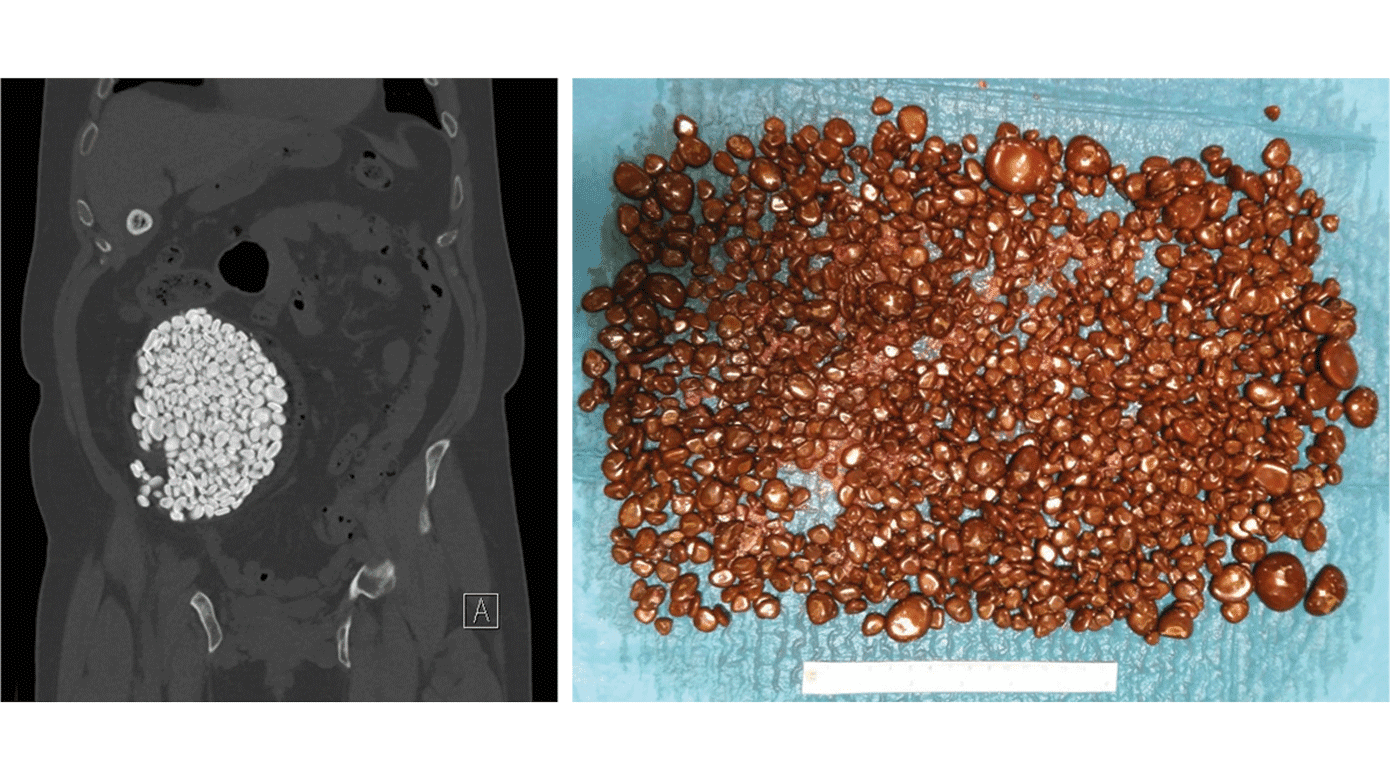

En 52-årig mand, som var blevet opereret for blæreekstrofi med Indiana pouch i 1994, var generet af manglende kapacitet, og en CT viste en fuldstændig udtamponeret pouch med sten. Indiana pouch er et kontinent urinreservoir bestående af terminale ileum samt højre colon, hvortil ureteres anastomoseres, og der tildannes urostomi, således at den ileale neourethra er tilgængelig for ren intermitterende kateterisation [1].

Af postoperative pouchrelaterede problemer er stendannelse en de hyppigste med incidens på ca. 10% [2, 3] med et medianstenantal på tre [4]. Der er ikke nogen standardbehandling for reservoirsten, men en enkelt eller multiple små sten kan behandles med nyrestensknusning (extracorporeal shock wave lithotripsy (ESWL)), transstomal eller perkutan nefrolitotomi, og for store sten kan laparotomi være passende [5]. I dette tilfælde valgtes med succes åben operation pga. det store stenvolumen, og der blev fjernet 1.185 sten med en samlet vægt på 840 g.